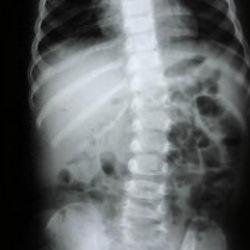

Hastanın durumunun son derece riskli olduğunu belirterek Prof. Dr. Köksal, “Zülbiye Hanım bize geldiğinde ileri derecede nefes darlığı vardı. Daha önce iki kez kalp ameliyatı geçirmişti ve bu kez triküspit kapağında ileri derecede kaçak vardı. 69 yaşında üçüncü bir kalp ameliyatı gerçekten çok ciddi riskler barındırır” dedi. Riskleri azaltmak için kapağı değiştirmek yerine tamir etmeyi tercih ettiklerini belirten Prof. Dr. Köksal, “Kapağın değiştirilmesi hem hayati riskleri artırır hem de hastanın ömür boyu daha yüksek doz kan sulandırıcı kullanmasına neden olur. Bu da ciddi kanama riskleri doğurur” diye belirtti.

“MADE IN TÜRKİYE” YÖNTEMİYLE TAMİR

Uygulanan yöntemin Türkiye’de geliştirildiğini vurgulayan Prof. Dr. Köksal, “Hastamızın triküspit kapağını, kendi geliştirdiğimiz ve ‘Made in Türkiye’ ismini verdiğimiz mitralizasyon yöntemiyle tamir ettik. Ayrıca ameliyatı sağ koltuk altından, endoskopik yöntemle ve kalbi durdurmadan gerçekleştirdik” diye konuştu. Bu yöntemin özellikle ileri yaş ve daha önce kalp ameliyatı geçirmiş hastalar için büyük avantaj sağladığını belirten Prof. Dr. Köksal, sözlerini şöyle tamamladı: “Küçük kesi, kalbi durdurmadan ameliyat ve kapak tamiri; teknolojinin bize sunduğu üç büyük avantaj. Yaşı kaç olursa olsun, her hastaya özel planlama yapıyoruz. En çok faydayı da bu hasta grubu görüyor.”